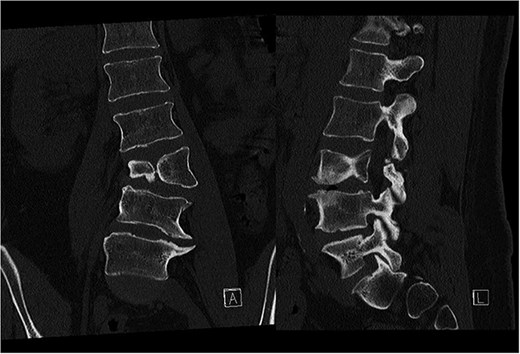

Last preoperative X-ray, lateral (A) and anteroposterior view (B). After 10 weeks of follow-up; lateral (C) and anteroposterior view (D). After 1 year of follow-up; lateral (E) and anteroposterior view (F).

Postoperatively, the patient experienced left psoas and quadriceps femoris muscle paresis, with the latter gradually improved to near-normal before discharge. No other complications were observed. At the 10-week follow-up, the left quadriceps had regained full strength, but partial paresis (3 out of 5) of the psoas muscle persisted, resulting in gait disturbance. At the final follow-up, one year after surgery, imaging showed L2-L4 fusion with no signs of instability or residual deformity (Fig. 4). The patient’s back pain resolved. A normal muscle function was observed.